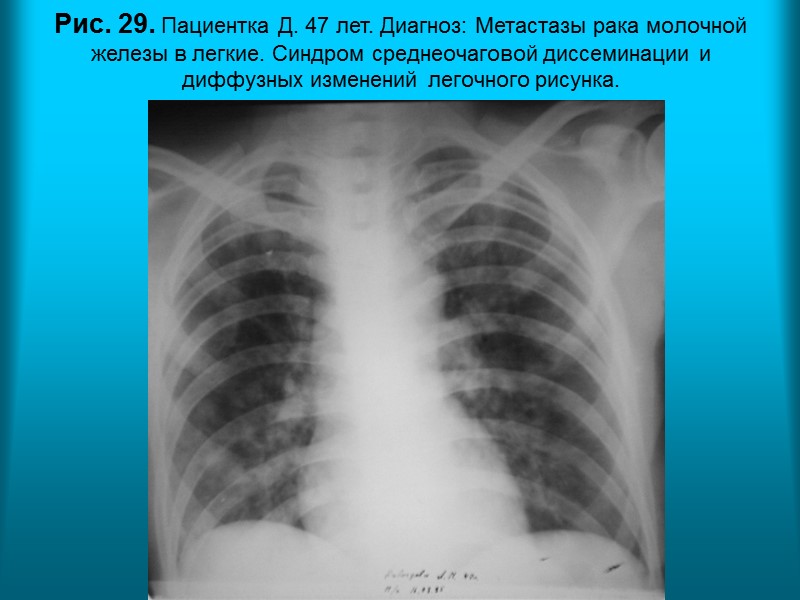

Н.С. Воротынцева. С.С. Гольев Рентгенопульмонология Рис. 29. Пациентка Д. 47 лет. Диагноз: Метастазы рака молочной железы в легкие. Синдром среднеочаговой диссеминации и диффузных изменений легочного рисунка.